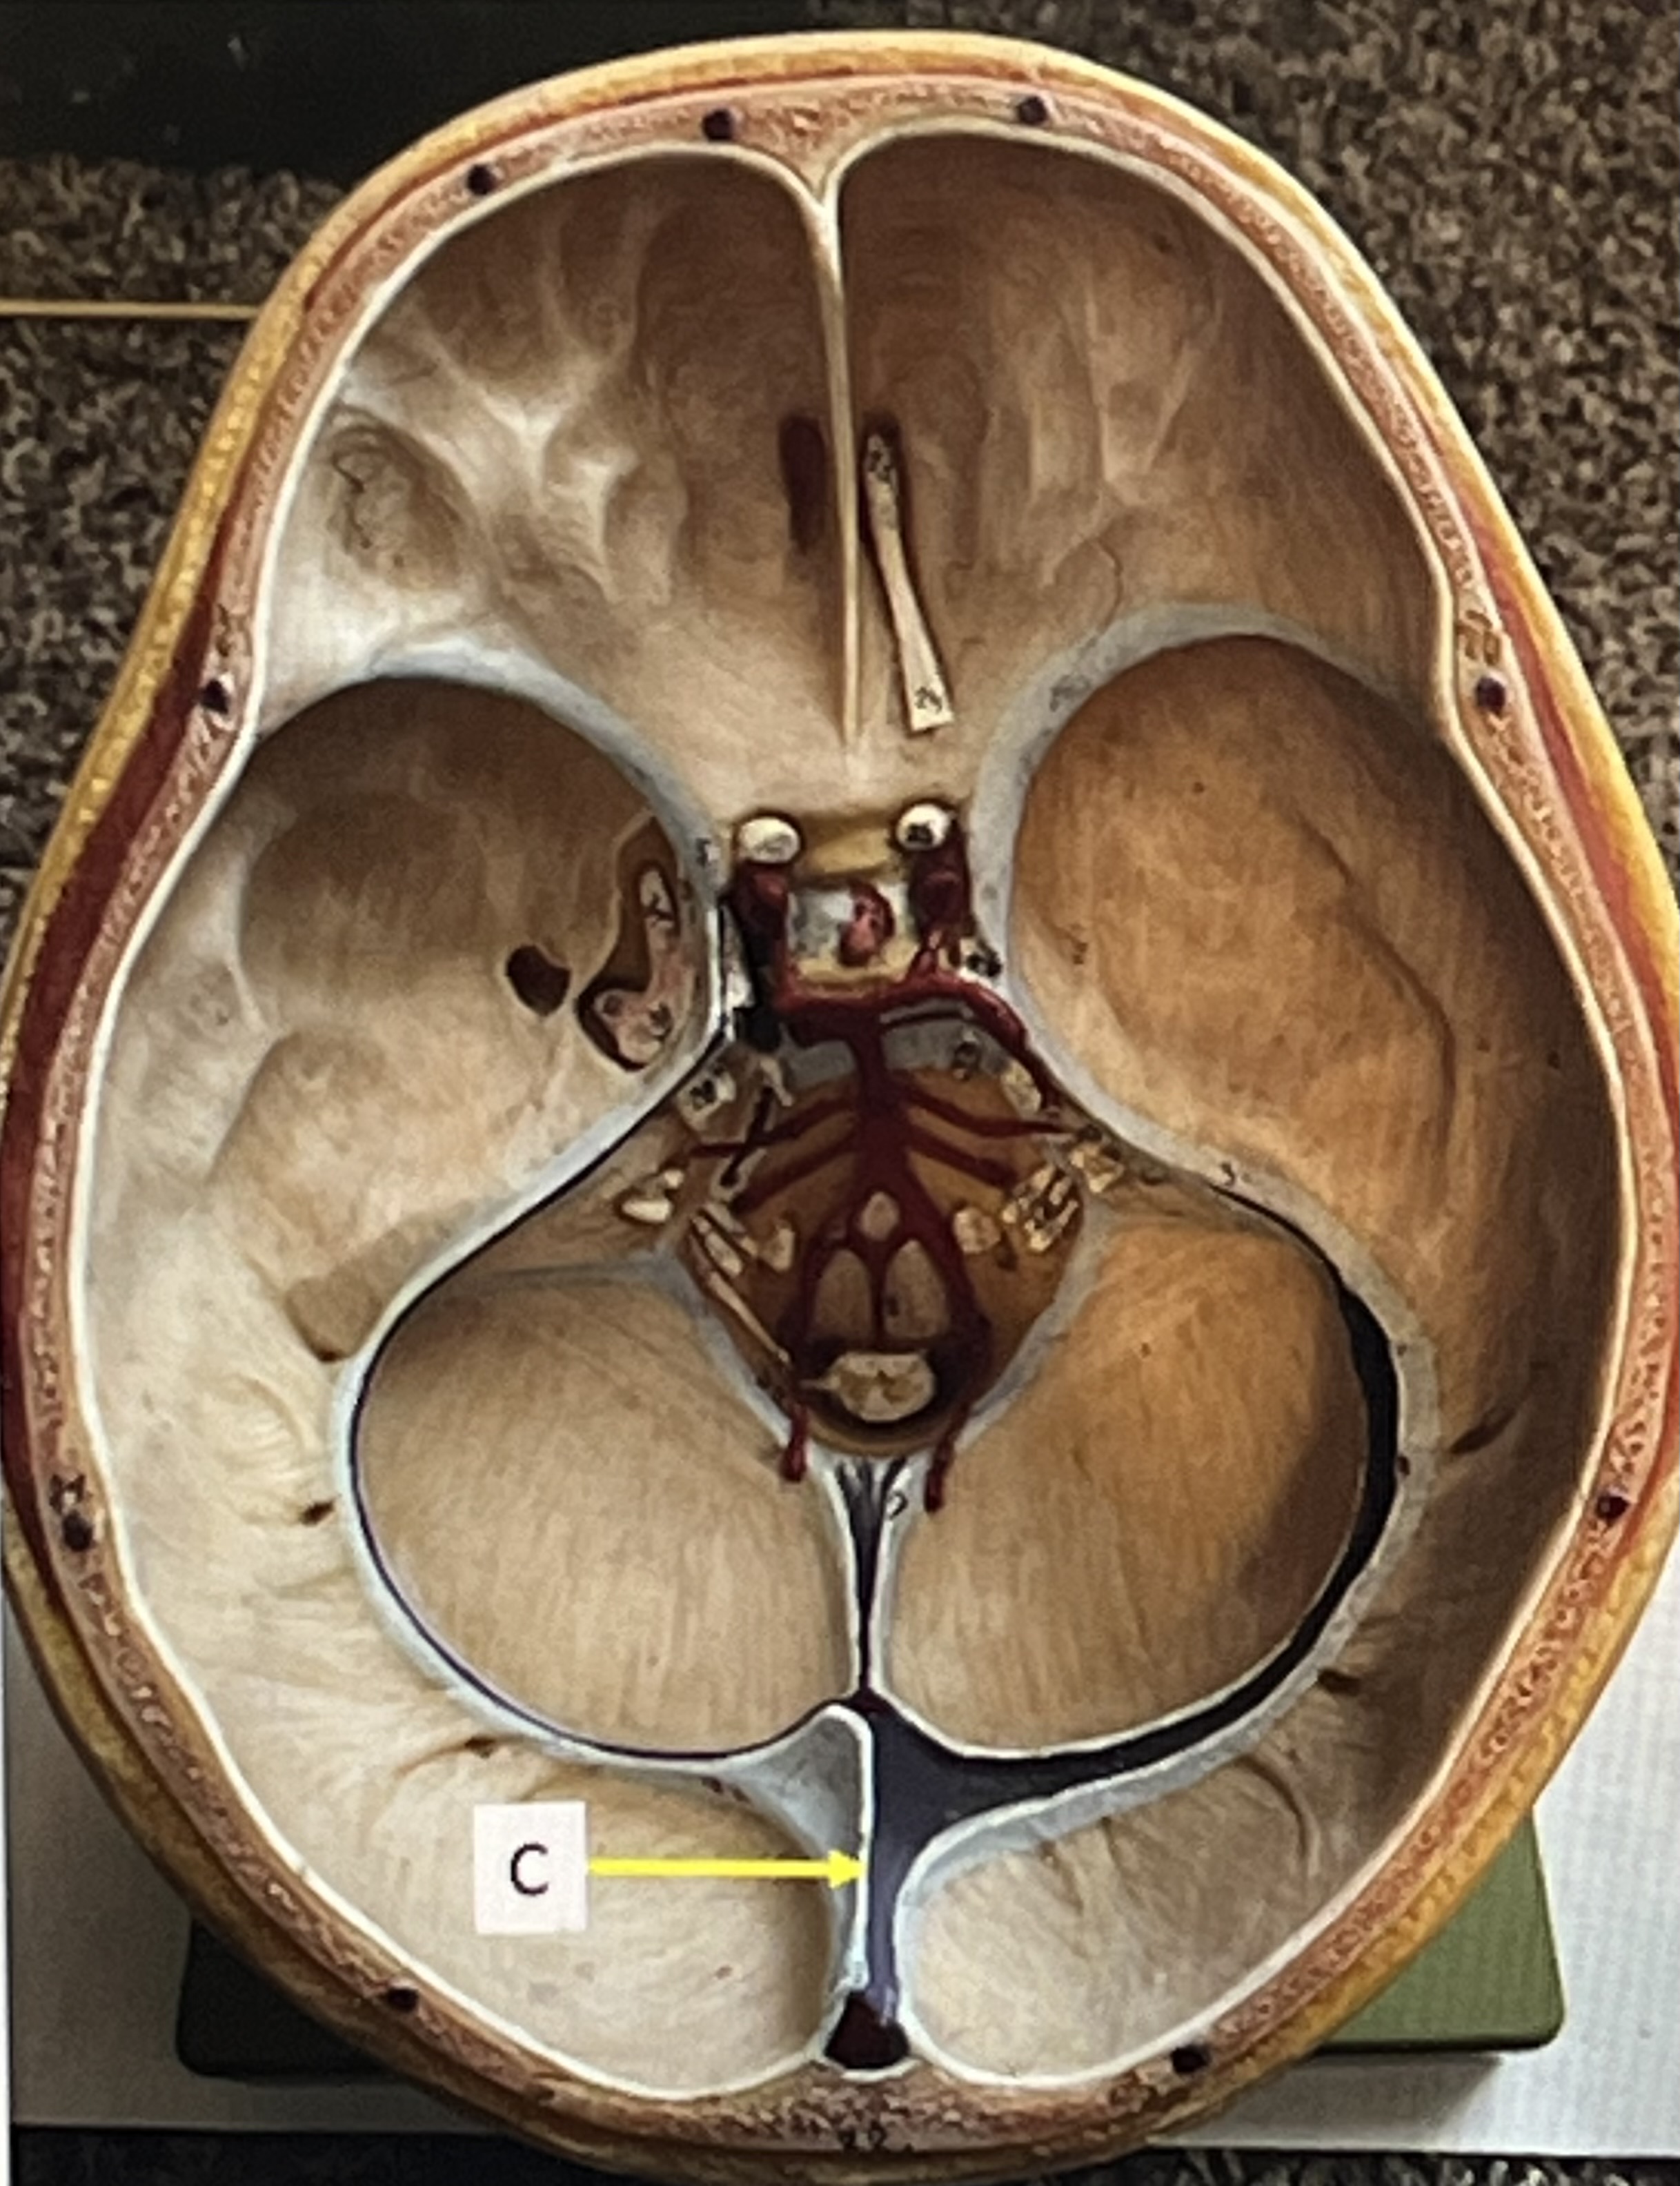

dura mater folds: falx cerebri

dura mater folds: falx cerebelli

dura mater folds: tentorium cerebelli

What is C?

3rd ventricle